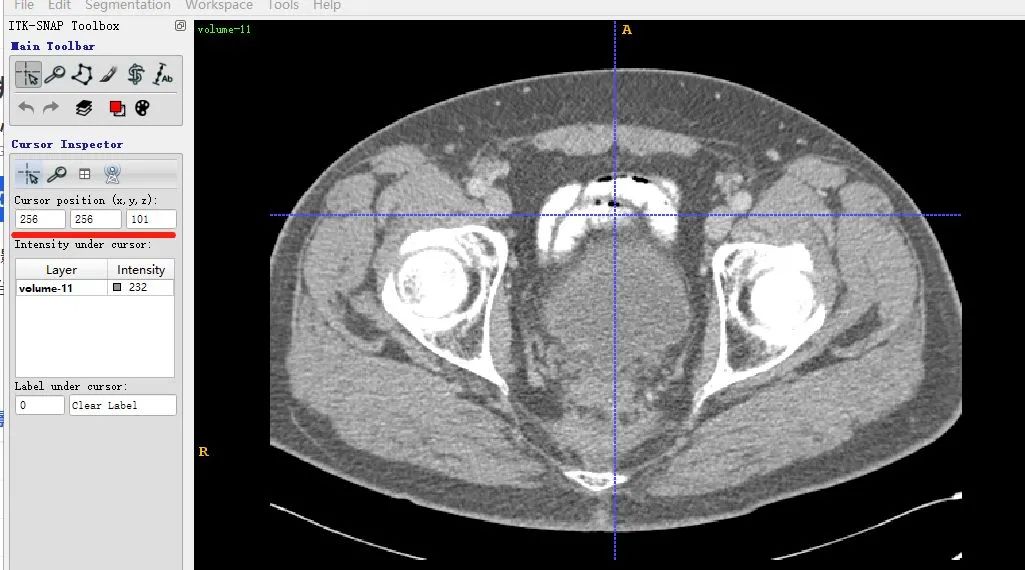

volume-11.nii (466, 512, 512) 232.0

This indicates the data shape is (466,512,512).

Note the order is z,x,y. z is the slice index. x and y are the width and height of a slice. Plot result for z index 100:

In ITK-SNAP the same slice is shown at coordinates (x,y,z) = (256,256,101) because ITK-SNAP uses 1-based indexing by default.

The X axes match between the two displays, but the Y axis is flipped due to differences in matplotlib display conventions. This does not indicate a mismatch in the loaded data.